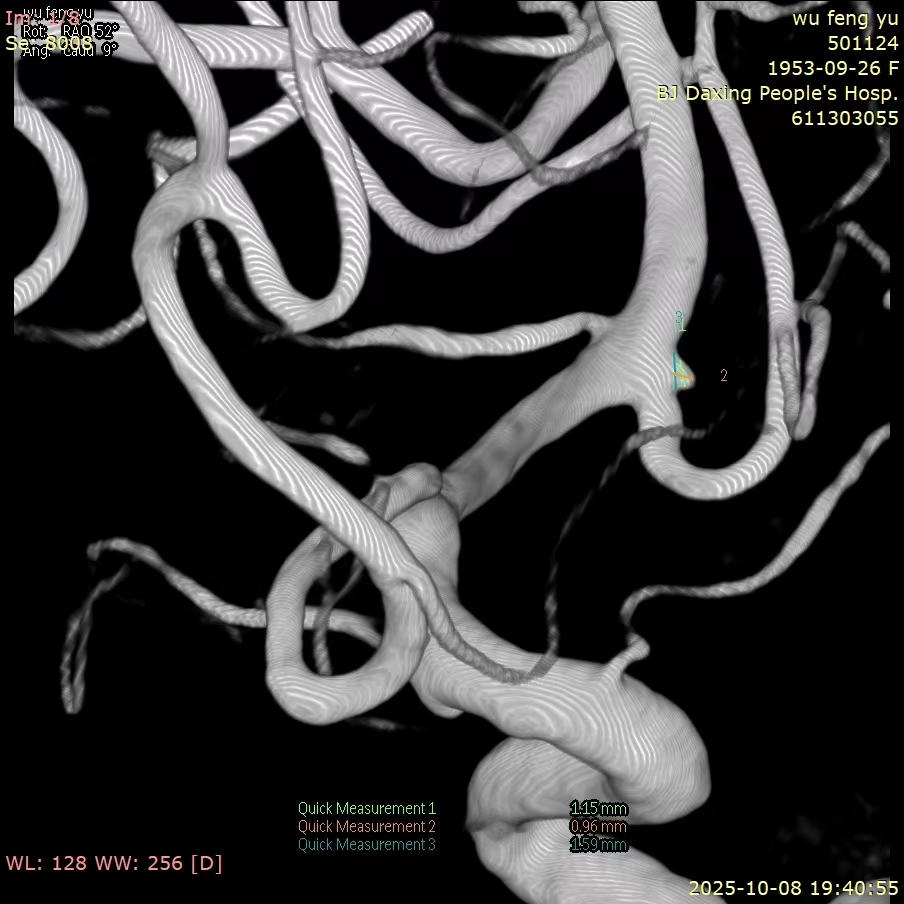

微小动脉瘤1例

患者老年女性,72岁,昏迷入院。